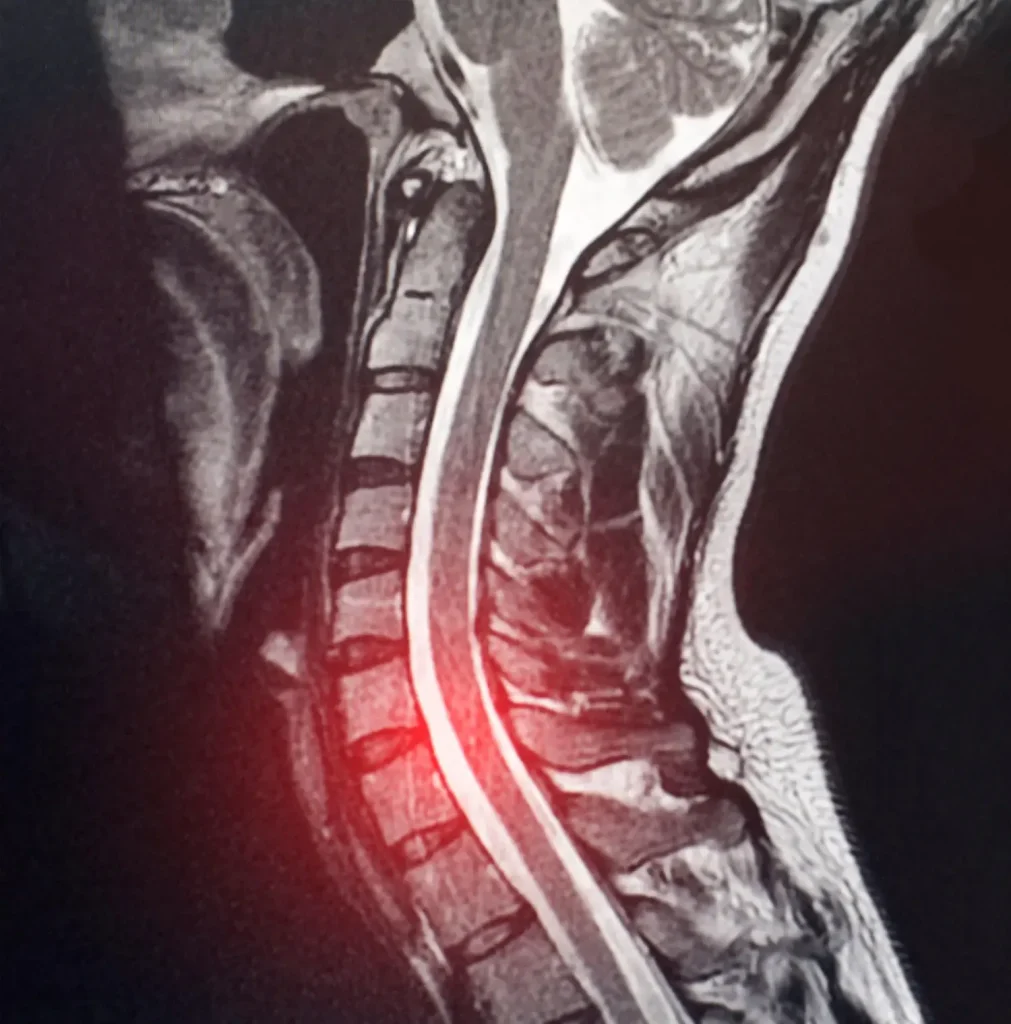

C6-C7 Disc Herniation MRI Showing Cervical Spine Compression

Magnetic Resonance Imaging (MRI): The gold standard for diagnosing cervical disc herniation. MRI provides detailed visualization of soft tissues, including the intervertebral discs, spinal cord, and nerve roots. It can reveal:

• The location and size of the disc herniation

• The degree of neural compression

• Spinal cord changes (if present)

• Other degenerative findings